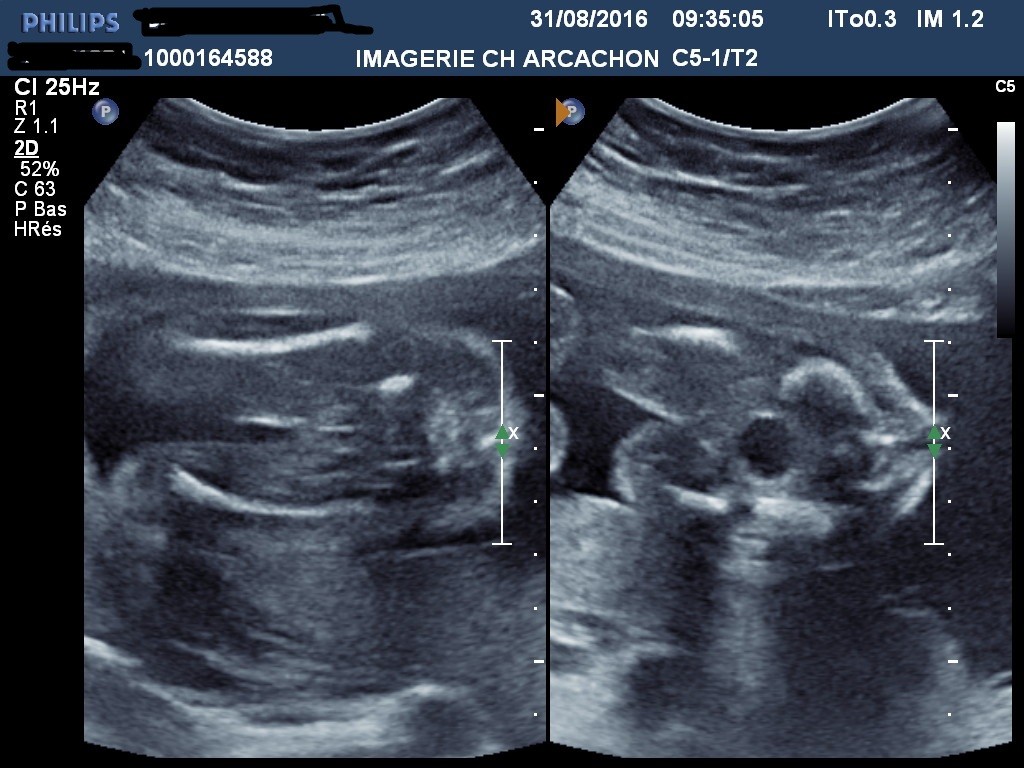

Video L Echographie A 21 Semaines De Grossesse Magicmaman Com

Echographie Du 25 Septembre 07 21 Semaines De Grossesse Vie De Bebe